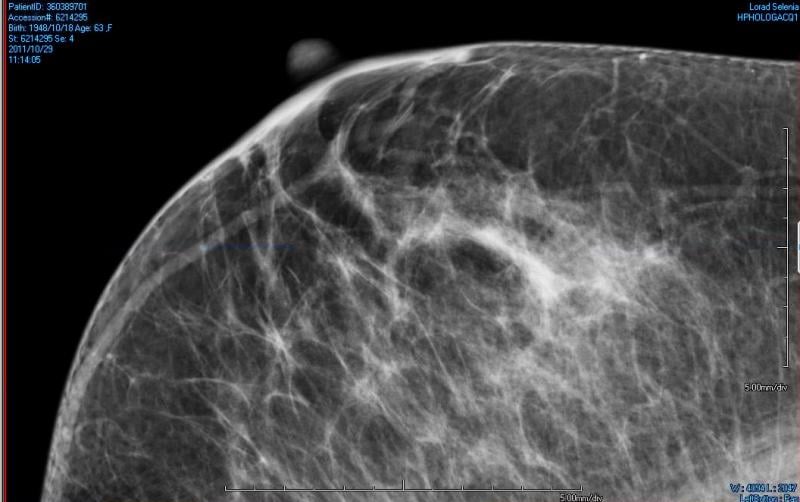

In a study appearing in the April 26 issue of JAMA, researchers examined the content, readability and understandability of dense breast notifications sent to women following screening mammography.

A new study from Elizabeth A. Rafferty, M.D., formerly of Massachusetts General Hospital, and colleagues evaluated the screening performance of digital mammography combined with tomosynthesis compared with digital mammography alone for women with varying levels of breast density.

Oklahoma Gov. Mary Fallin signed HB2601 into law, making the Oklahoma the 26th state to report a patient's breast tissue composition through the mammography reporting results.

Despite decades of progress in breast imaging, one challenge continues to test even the most skilled radiologists ...